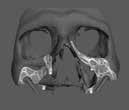

A korai harmicas éveiben járó hölgy rendelőnkbe érkezésének oka a jobb felső nagymetsző fog bizonytalan érzkenysége, elmondása alapján gyermekkorában trauma érte a felső frontrégiót. A frakturált klinikai koronákat kompozittöméssel helyreállították, egyéb kezelést akkor nem tartottak szükségesnek. Az utóbbi hónapokban tapasztalt érzékenység miatt kereste fel rendelőnket. A klinikai vizsgálat (1. és 2. kép) és a CBCT felvétel (3. kép) alapján diagnosztizált külső gyökérreszorpció megoldására a fog eltávolítását, implantátum

bukkális 1. kép: Kiindulási állapot, 2020. január. 3. kép: Kiindulási CBCT felvétel. 2. kép: Kiindulási állapot a palatinális oldal felől.